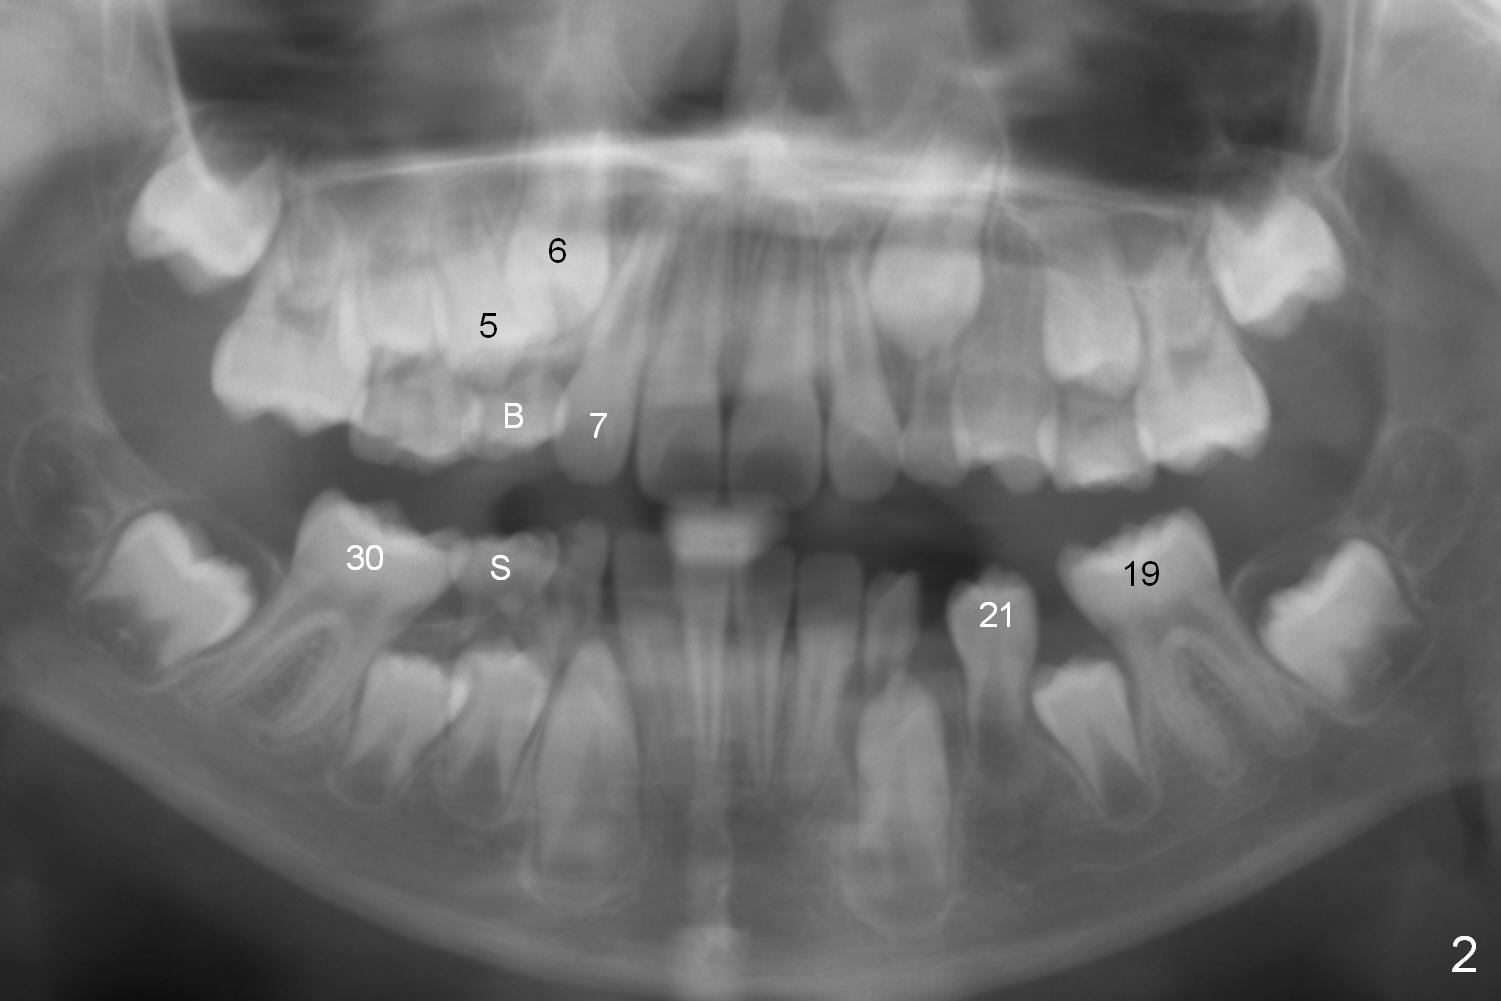

At age of 6 years 1 month, Linwei (boy) has crowding problem, especially in the lower right quadrant (Fig.1). At 9, the crowding also involves the upper right and lower left quadrants (Fig.2). A bilateral space regainer is placed for the lower arch a month later.